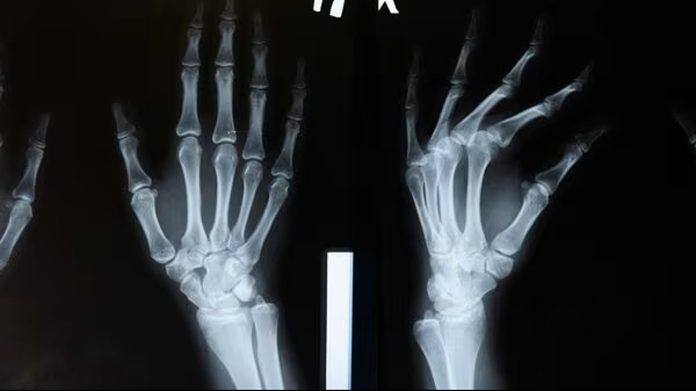

تمكّن فريق بحثي في الصين من تحقيق إنجاز طبي كبير، وهو تطوير “غراء عظمي” جديد يسمى Bone-02، قادر على تثبيت الشظايا العظمية المكسورة خلال 3 دقائق فقط. هذا الابتكار، الذي استُلهم من كيفية التصاق المحار تحت الماء، يمثل نقلة نوعية في مجال جراحة العظام.

يتميز الغراء الجديد بسرعة تثبيته وفعاليته حتى في البيئات الغنية بالدم. والأهم من ذلك، أنه قابل للامتصاص داخل الجسم، مما يلغي الحاجة إلى إجراء عمليات جراحية إضافية لإزالة المسامير والصفائح المعدنية التقليدية.

وأظهرت الاختبارات المعملية والسريرية نجاحًا كبيرًا للمادة. فقد أثبتت التجارب التي أُجريت على أكثر من 150 مريضًا أنها آمنة وفعالة، وتوفر قوة ربط عالية.

ويأمل الباحثون أن يمهد هذا الابتكار الطريق لتقليل المضاعفات وتسريع زمن العمليات الجراحية، مما يجعله بديلاً واعداً للمزروعات المعدنية التقليدية.